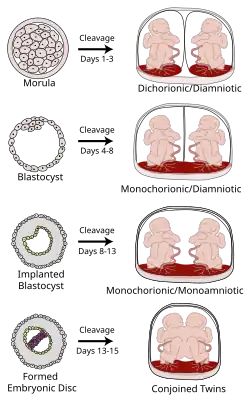

Degree of separation

Various types of chorionicity and amniosity (how the fetus' sac looks) in monozygotic (identical) twins as a result of when the fertilized egg divides

The degree of separation of the twins in utero depends on if and when they split into two zygotes. Dizygotic twins were always two zygotes. Monozygotic twins split into two zygotes at some time very early in the pregnancy. The timing of this separation determines the chorionicity (the number of placentae) and amniocity (the number of sacs) of the pregnancy. Dichorionic twins either never divided (i.e.: were dizygotic) or they divided within the first four days. Monoamnionic twins divide after the first week.

In very rare cases, twins become conjoined twins. Non-conjoined monozygotic twins form up to day 14 of embryonic development, but when twinning occurs after 14 days, the twins will likely be conjoined.[45] Furthermore, there can be various degrees of shared environment of twins in the womb, potentially leading to pregnancy complications.

It is a common misconception that two placentas automatically implies dizygotic twins, but if monozygotic twins separate early enough, the arrangement of sacs and placentas in utero is in fact indistinguishable from that of dizygotic twins.

Dichorionic–diamniotic Normally, twins have two separate (di- being a numerical prefix for two) chorions and amniotic sacs, termed dichorionic–diamniotic or DiDi. It occurs in almost all cases of dizygotic twins (except in very rare cases of fusion between their blastocysts[46]) and in 18–36%[47] (or around 25%[46]) of monozygotic (identical) twins.

Dichorionic–diamniotic twins form when splitting takes place by the third day after fertilisation.[46]

Monochorionic twins generally have two amniotic sacs (called monochorionic–diamniotic MoDi), which occurs in 60–70% of the pregnancies with monozygotic twins,[47] and in 0.3% of all pregnancies.[49] Monochorionic–diamniotic twins are almost always monozygotic, with a few exceptions where the blastocysts have fused.[46]

Monochorionic–monoamniotic Monochorionic twins share the same amnion in 1–2% of monozygotic twin pregnancies.[47]

Monoamniotic twins occur when the split takes place after the ninth day after fertilization.[46]

If the division of the zygote occurs later than the 12 days then conjoined twins are usually the result.